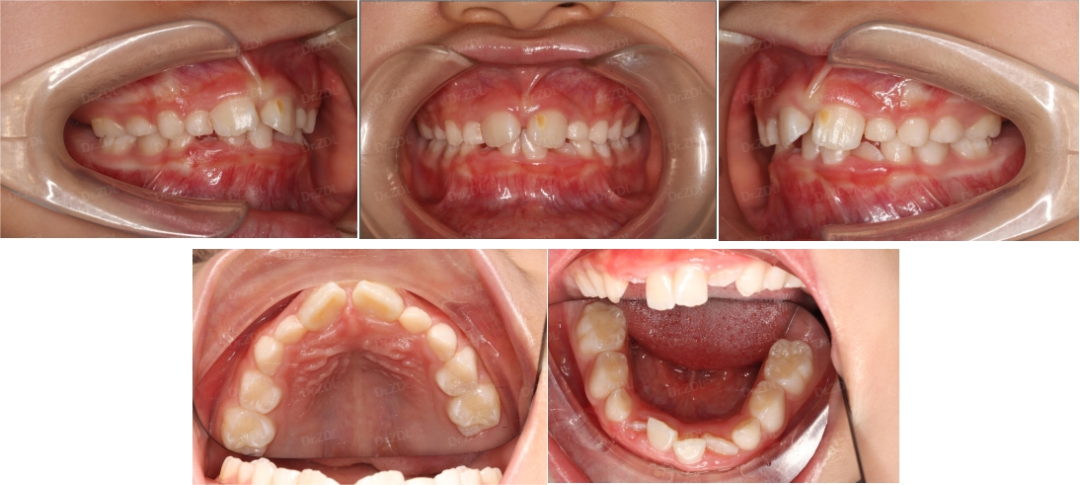

Grace硅胶牙套案例1:

像这位8岁小朋友主诉门牙有缝、牙不齐、嘴凸,家长也比较重视孩子的口腔健康和颌面发育问题。根据牙片资料和口内检查发现,孩子恒牙胚数量无缺失,牙根发育正常,骨性I类,均角面型,生长方向正常,上前牙唇倾不齐,上颌稍前突,下颌稍后缩。

根据孩子牙齿情况,采用Grace轨道式硅胶矫治器,恢复上下颌正常牙弓宽度,匹配上下颌牙弓形态,引导上下恒牙正常萌出,引导下颌前伸,并日常辅助唇肌功能训练。

Grace佩戴6个月,上颌中切牙间隙完全关闭,牙弓形态调整良好,下前牙萌出排齐良好。